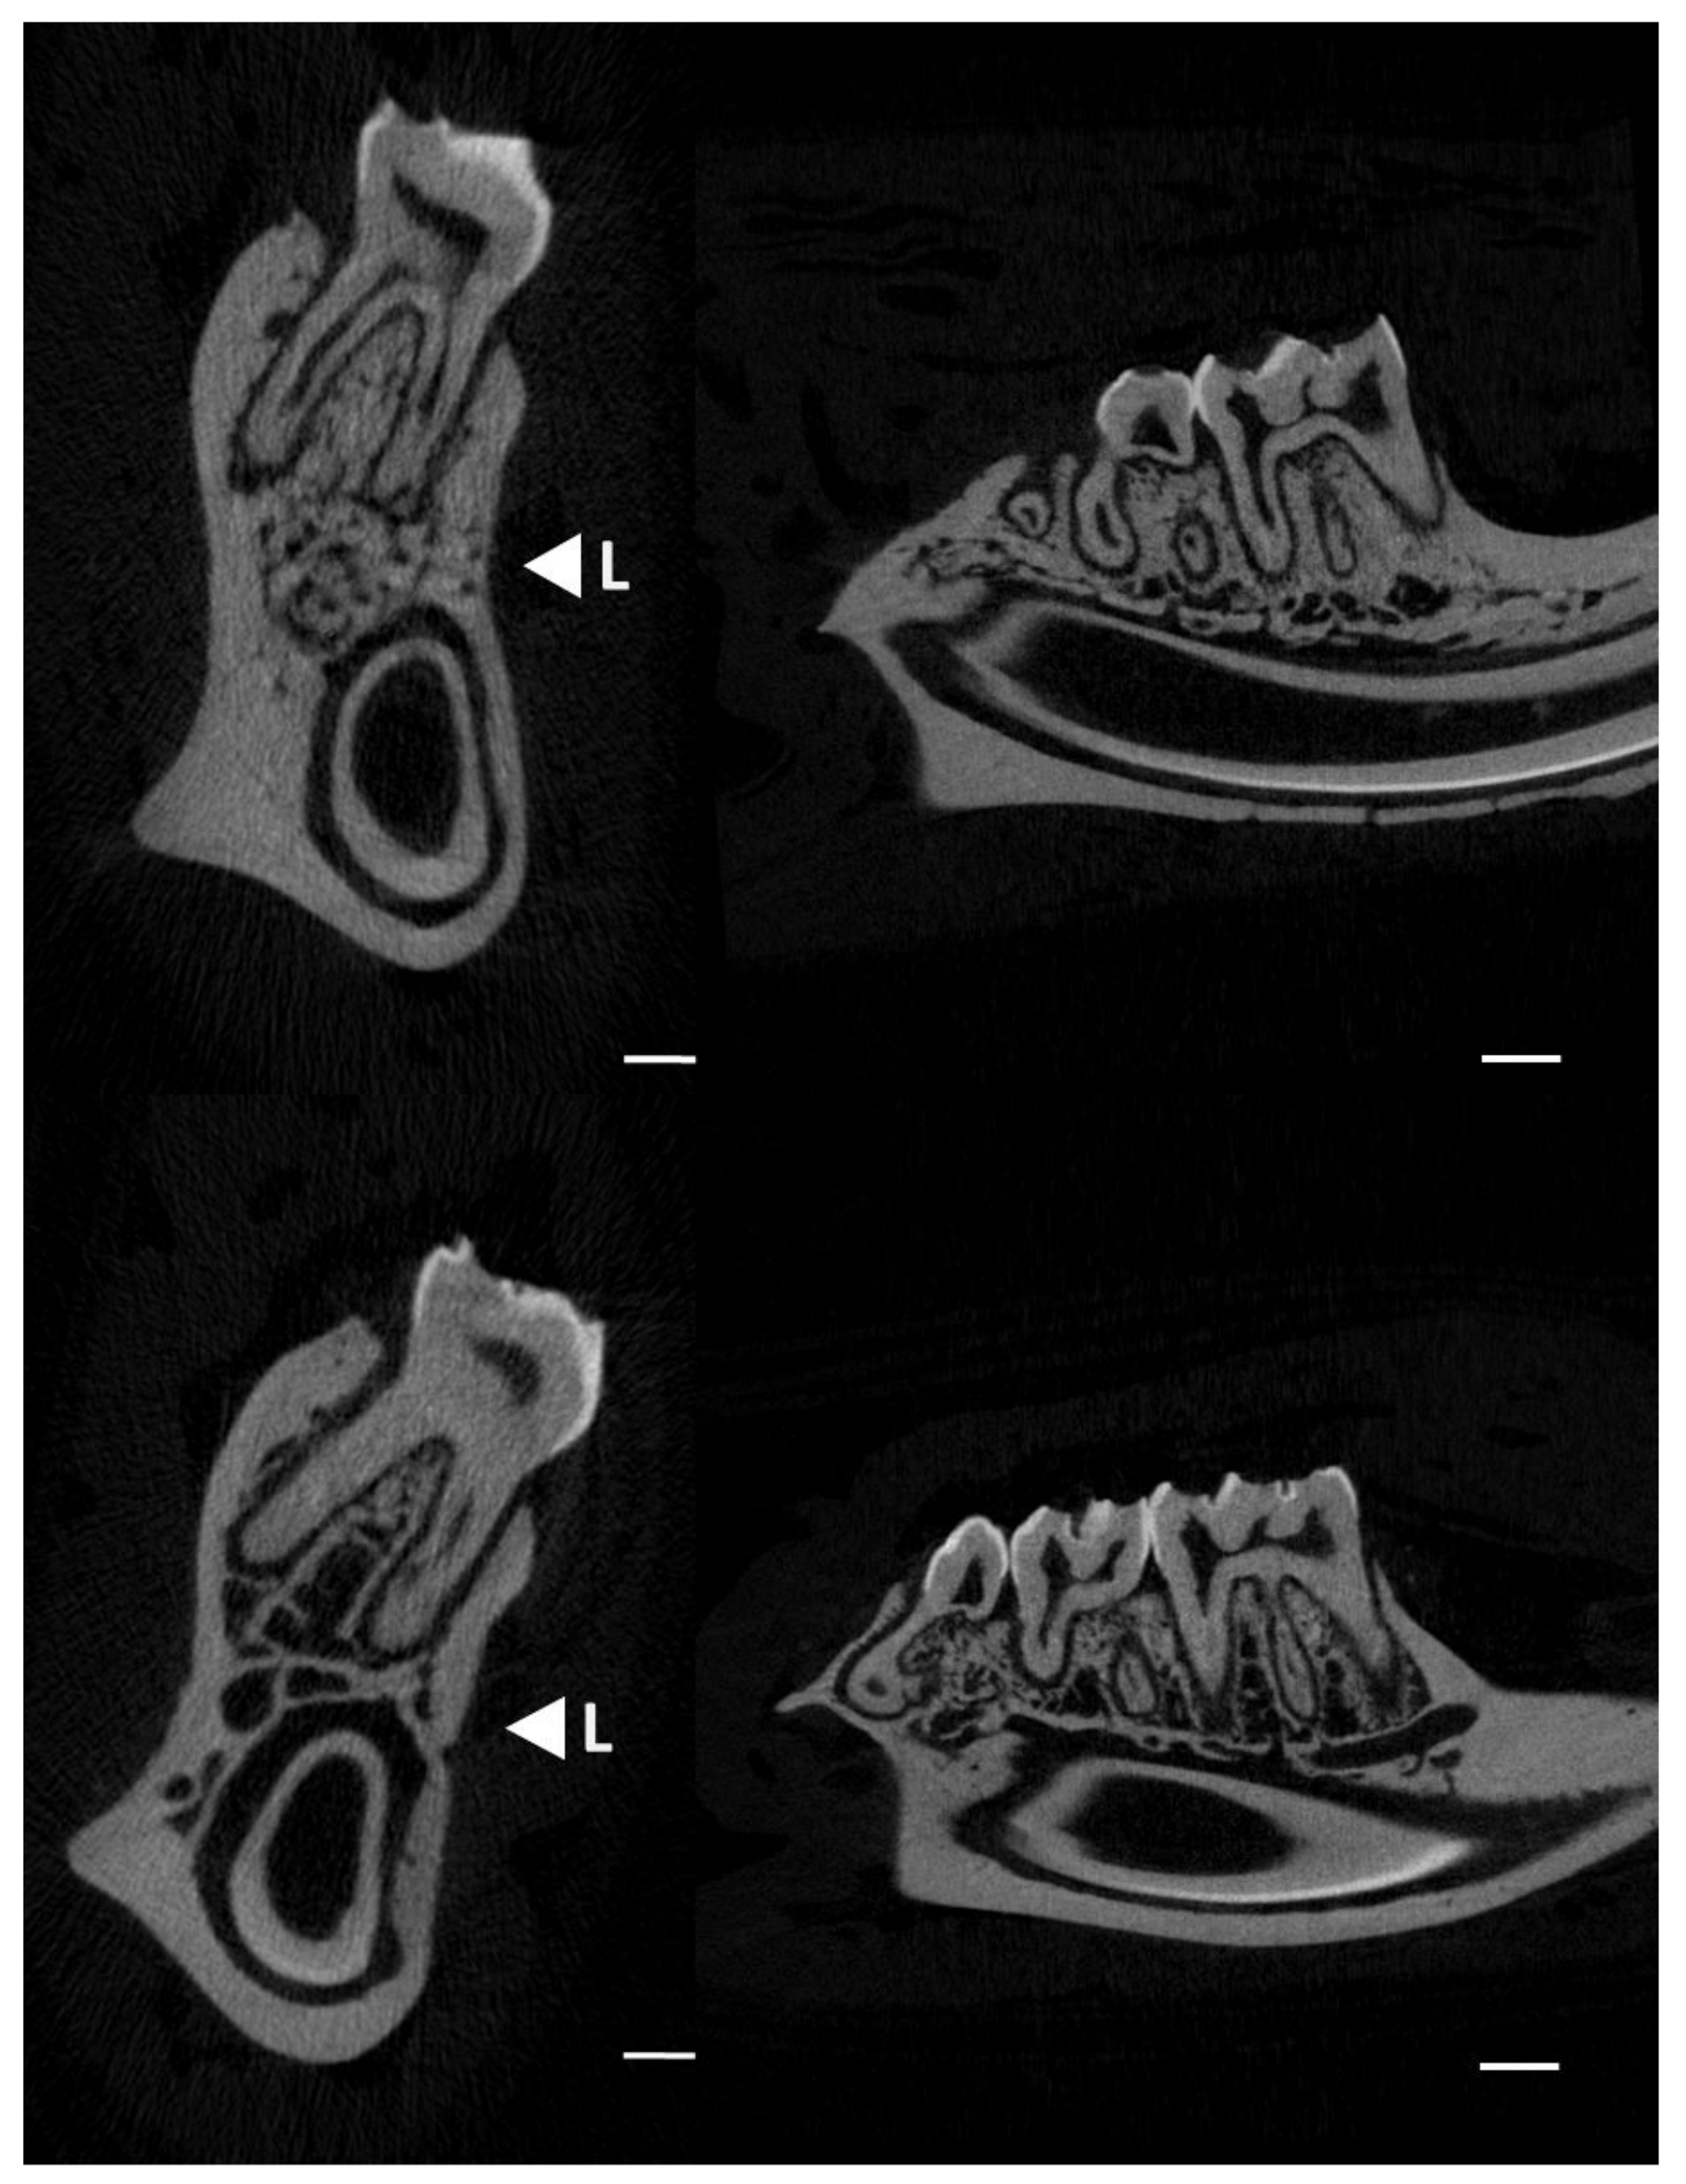

2.2. Micro-CT Analyses

3.1. Micro-Architectural Characteristics